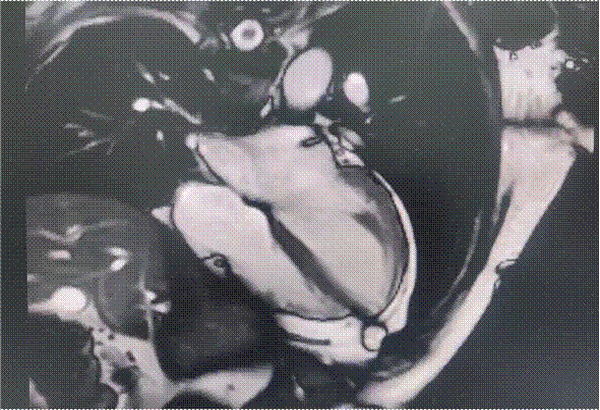

心脏电影成像